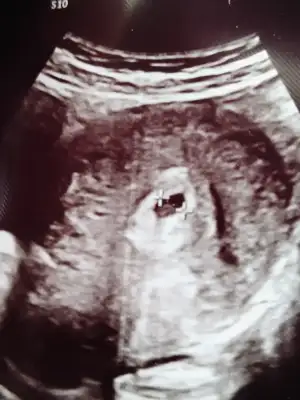

Yumurtlama günümde başlayan göğüs ağrısı ve akıntım vardı akıntım azaldı ama göğüs ağrım hiç geçmedi evde test yaptım yumurtlamanın 10 gününde silik çizgi vardı bekleyip 12 günü bı test daha yaptım koyulasmisti kan verdim 70 çıktı şimdi salı gününü bekliyorum tekrar kan verecem ilk resim yumurtlamadan 10 gün sonra ikinci resim 12 gün v kan değeri 70 ve göğüs ağrım hala geçmedi